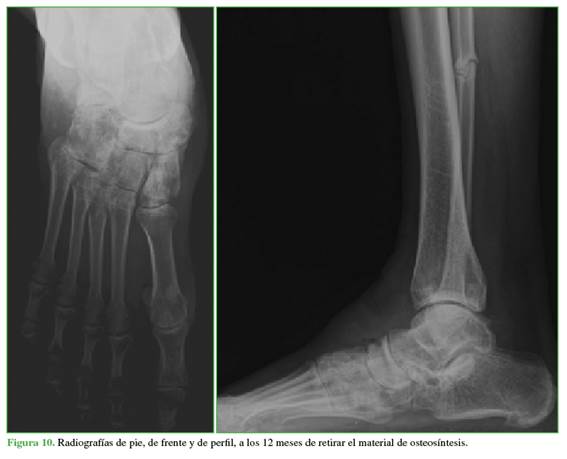

Se retiró la sutura a los 15 días, las heridas tuvieron una buena evolución y se planificó el retiro del material de osteosíntesis a los cinco meses, porque los implantes fueron colocados en puente a través de la articulación calcaneocuboidea y astragalonaviculo-cuneiforme hasta permitir la cicatrización ligamentaria. No se observaron signos de necrosis del hueso navicular. Se evaluó la presencia de artrosis en las articulaciones calcaneocuboidea, astragalonaviculo-cuneiforme y subastragalina al año de seguimiento, que no se correlacionó con los síntomas del paciente (Figura 10). Se detectó artrosis grado 1 en las diferentes articulaciones.15